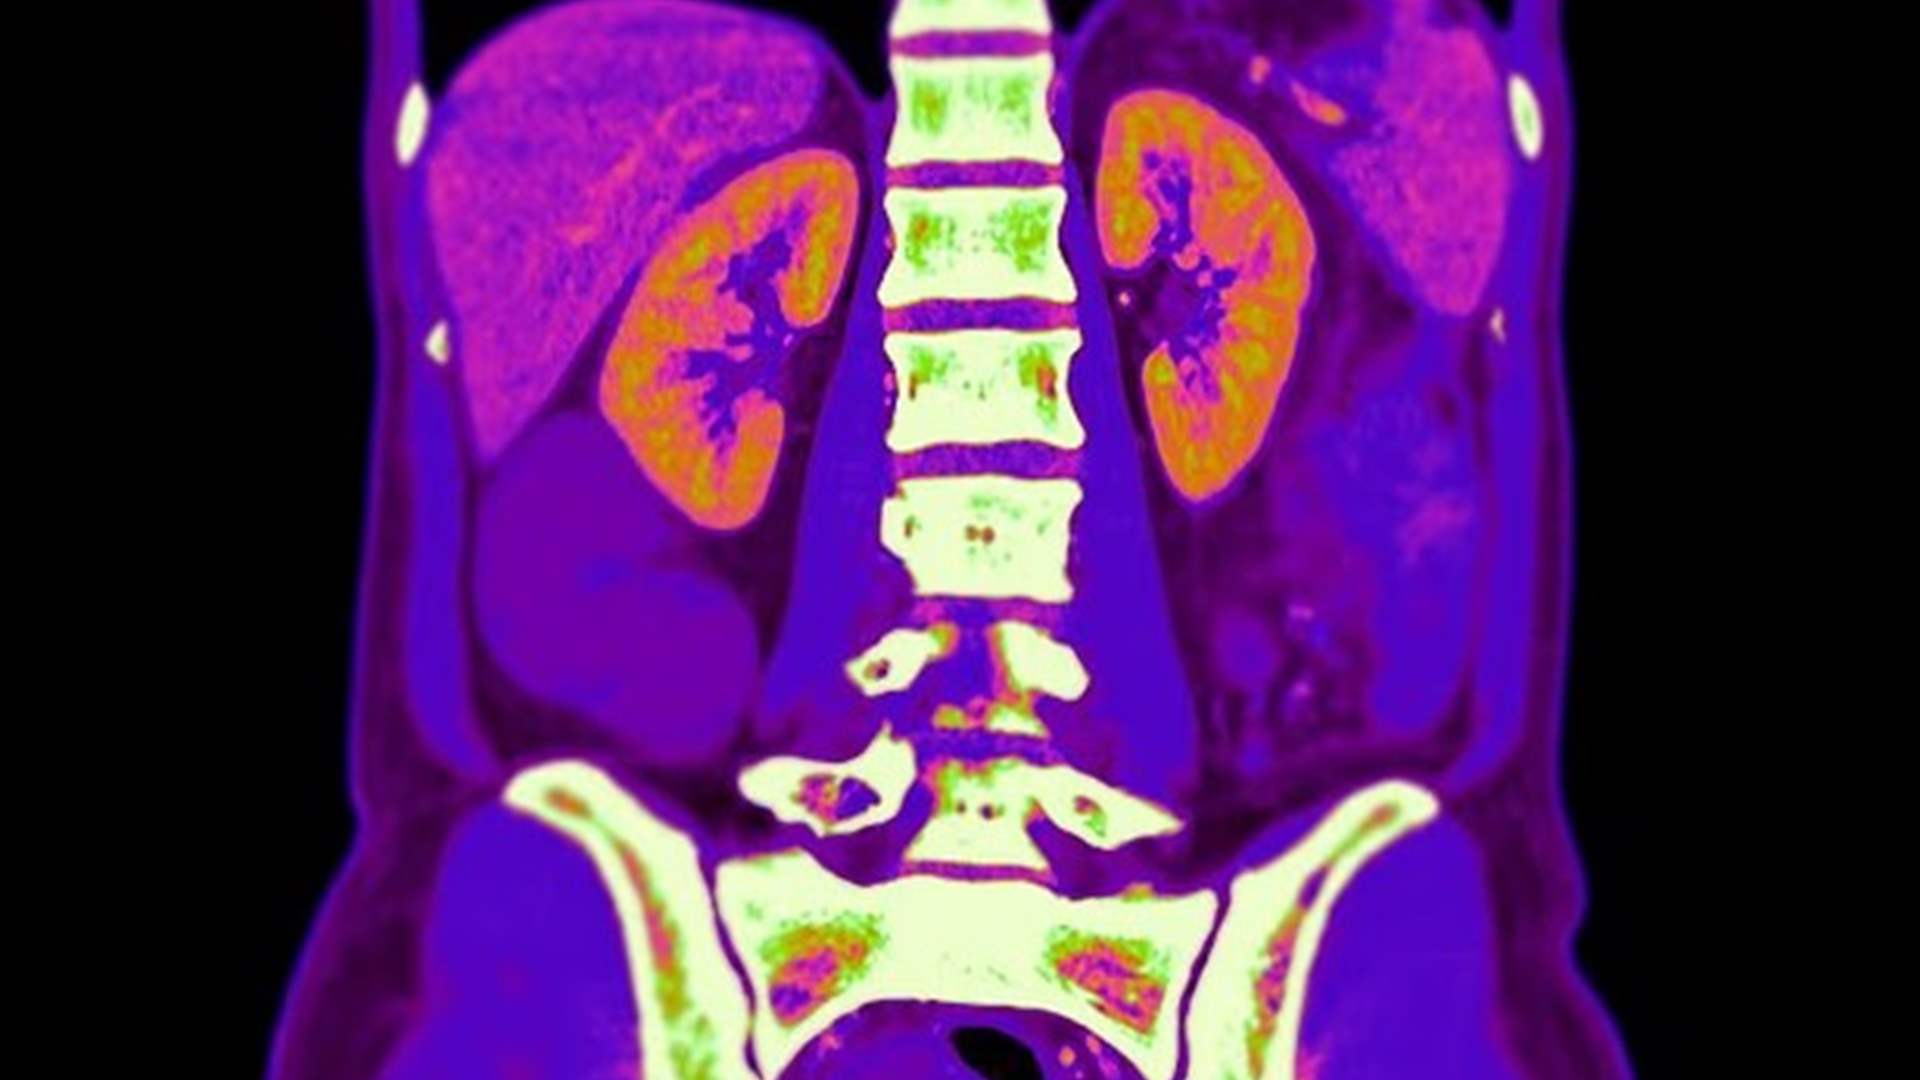

فحص شائع قد يرفع خطر السرطان... وخبراء يحذرون من مخاطره التراكمية

كشفت دراسة حديثة نُشرت في مجلة JAMA Internal Medicine أنّ فحص التصوير الطبقي المحوري (CT Scan) للبطن يمكن أن يعرّض الجسم لمستوى إشعاعي يعادل نحو 90 صورة أشعة للصدر، ما يسلّط الضوء على المخاطر الصحية المحتملة لهذا النوع من الفحوصات التي يُعتقد بأنها آمنة.

وبدأت القصة مع امرأة خضعت لفحص سكانر قبل ثماني سنوات، بعد معاناتها من فقدان وزن سريع، وتعرّق ليلي حاد، وضبابية ذهنية، وإرهاق عام. ورغم أن فحوص الدم لم تُظهر خللًا، أحالها الطبيب إلى فحص سكانر للبطن والحوض. ما لم تكن تعرفه آنذاك هو أن جسمها تلقى 9.1 ميلليزيفرت من الإشعاع خلال ثوانٍ معدودة — وهي كمية تُعادل السفر جواً عبر الأطلسي أكثر من 100 مرة أو 450 صورة أشعة للصدر.

وتقدّر الدراسة الحديثة أن نحو 93 مليون فحص CT تم إجراؤها في الولايات المتحدة عام 2023 فقط، قد تؤدي إلى أكثر من 100,000 حالة سرطان محتملة — أي أن واحدة من كل 20 إصابة بالسرطان قد تكون مرتبطة بفحوصات الأشعة، وفق ما نقل موقع

دايلي ميل

.

ويستخدم فحص الـCT الإشعاع المؤين، الذي يمكن أن يتسبب بكسر الحمض النووي داخل الخلايا، ويخلق جزيئات حرة ضارة قد تساهم في نشوء السرطان مع الوقت. ولأن الفحص يركّز الأشعة على منطقة معيّنة من الجسم، فإن الأعضاء الحساسة قد تتعرض للإشعاع أكثر من مرة في الجلسة الواحدة، إضافة إلى الجرعات التراكمية الناتجة عن الفحوص المتكررة.

ويبحث علماء من هارفارد وناسا في كيفية ترميم الضرر "الخفي" الذي تُسببه هذه الأشعة على مستوى الجينات. الدكتور ديفيد سينكلير، أستاذ علم الوراثة في جامعة هارفارد، قال إن الإشعاع قد يُحدث كسورًا صغيرة في الحمض النووي تخلّ بتنظيم الجينات، وتسرّع الشيخوخة، وترفع خطر الإصابة بالسرطان.

وأضاف: "لم أخضع لفحص سكانر في حياتي، ولن أفعل إلا إذا كان الأمر ضروريًا جدًا".

وحذر الخبراء من أن العمر يلعب دورًا مهمًا، فالأجسام الأصغر سنًا قد تكون أكثر عرضة لتراكم الأضرار على مدى السنوات.

وفي ظل هذه التحذيرات، يدعو الأطباء إلى الحذر وعدم الإفراط في إجراء فحوص CT إلا عند الضرورة القصوى، مع ضرورة توعية المرضى بكمية الإشعاع التي قد يتعرضون لها.